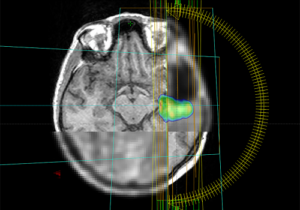

Mehr erfahren zu: "Mutationsspezifischer Peptidimpfstoff gegen Mittellinien-Gliome erstmals bei Patienten eingesetzt" Mutationsspezifischer Peptidimpfstoff gegen Mittellinien-Gliome erstmals bei Patienten eingesetzt Tumorimpfungen können den Körper im Kampf gegen Krebs unterstützen. Diese Vakzine machen das Immunsystem der Patienten auf krebstypisch veränderte Proteine aufmerksam. Mediziner und Krebsforscher aus Heidelberg und Mannheim haben nun […]